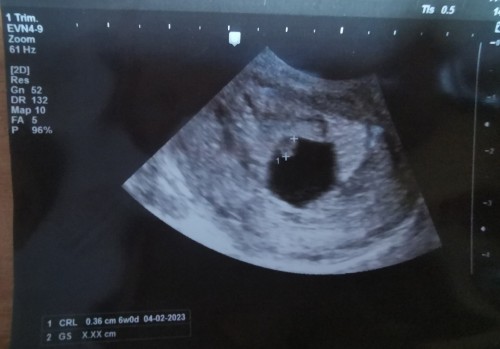

Đọc thêmตอน 7 วีค ไปหาหมอ ตอนนั้นเจอแต่ถุงตั้งครรภ์ค่ะ ใจก็ไม่ค่อยจะดีเท่าไร ครั้งนี้ เข้าห้องน้ำแล้วเจอเลือดออกสีชมพูๆ เช็คอีกทีมีลิ่มเลือด เล็กมากๆๆ ติดออกมา เลยรีบไปพบคุณหมอค่ะ คุณหมออัลตร้าซาวด์ให้ทางช่องคลอด เจอตัวน้องแล้วค่ะขนาด 0.36 cm แต่กลับไม่ได้ยินเสียงหัวใจ 😭 ตอนนี้แม่กังวลมากค่ะ กลัวน้องไม่อยู่ ท้องแรกค่ะ